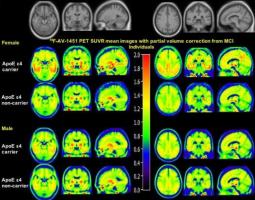

Actualité publiée il y a 5 années 1 semaineALZHEIMER : Le sexe affecte tau dans le cerveau